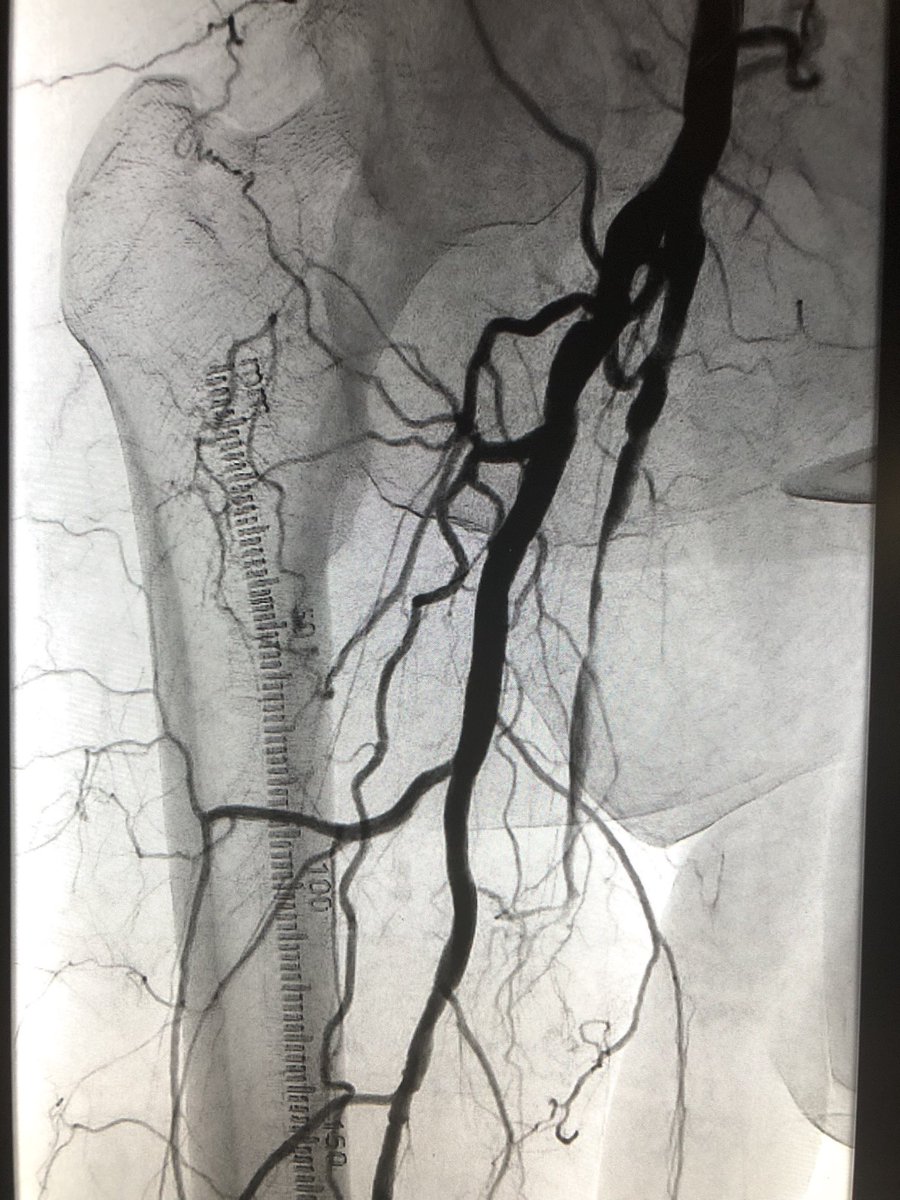

@JChurches @SriniTummala @thegestgroup @SIRspecialists @CAIRweb @TraineesBSIR @SIRRFS @SIR_ECS @VIVAPhysicians @ISETNews @ISEVSonline @BSIR_News @VascularSVS @ACCinTouch @Balt_Group @KyleObradovich @LindsayKThornt1 @bostonsci @MDTVascular @MountSinaiIR Forgot to add @MikePatelMD. Amazing resident. Even better fellow.